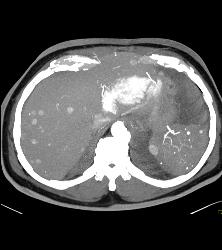

Renal Cell Carcinoma Metastatic to the Heart -right Atrium and Ventricle